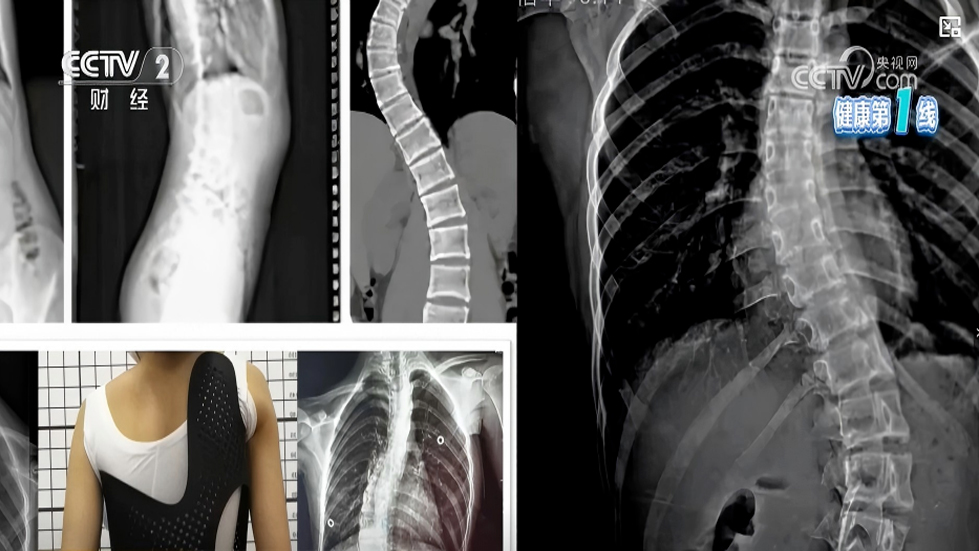

脊柱侧弯保守治疗全解析|非手术手段,专业科普一看就懂

脊柱侧凸是一种复杂的脊柱三维畸形,国际脊柱侧凸研究学会(SRS)明确将其定义为:在站立位全脊柱冠状面X线片测量Cobb角≥10°。其中,特发性脊柱侧凸病因尚不明确,约占脊柱侧凸...